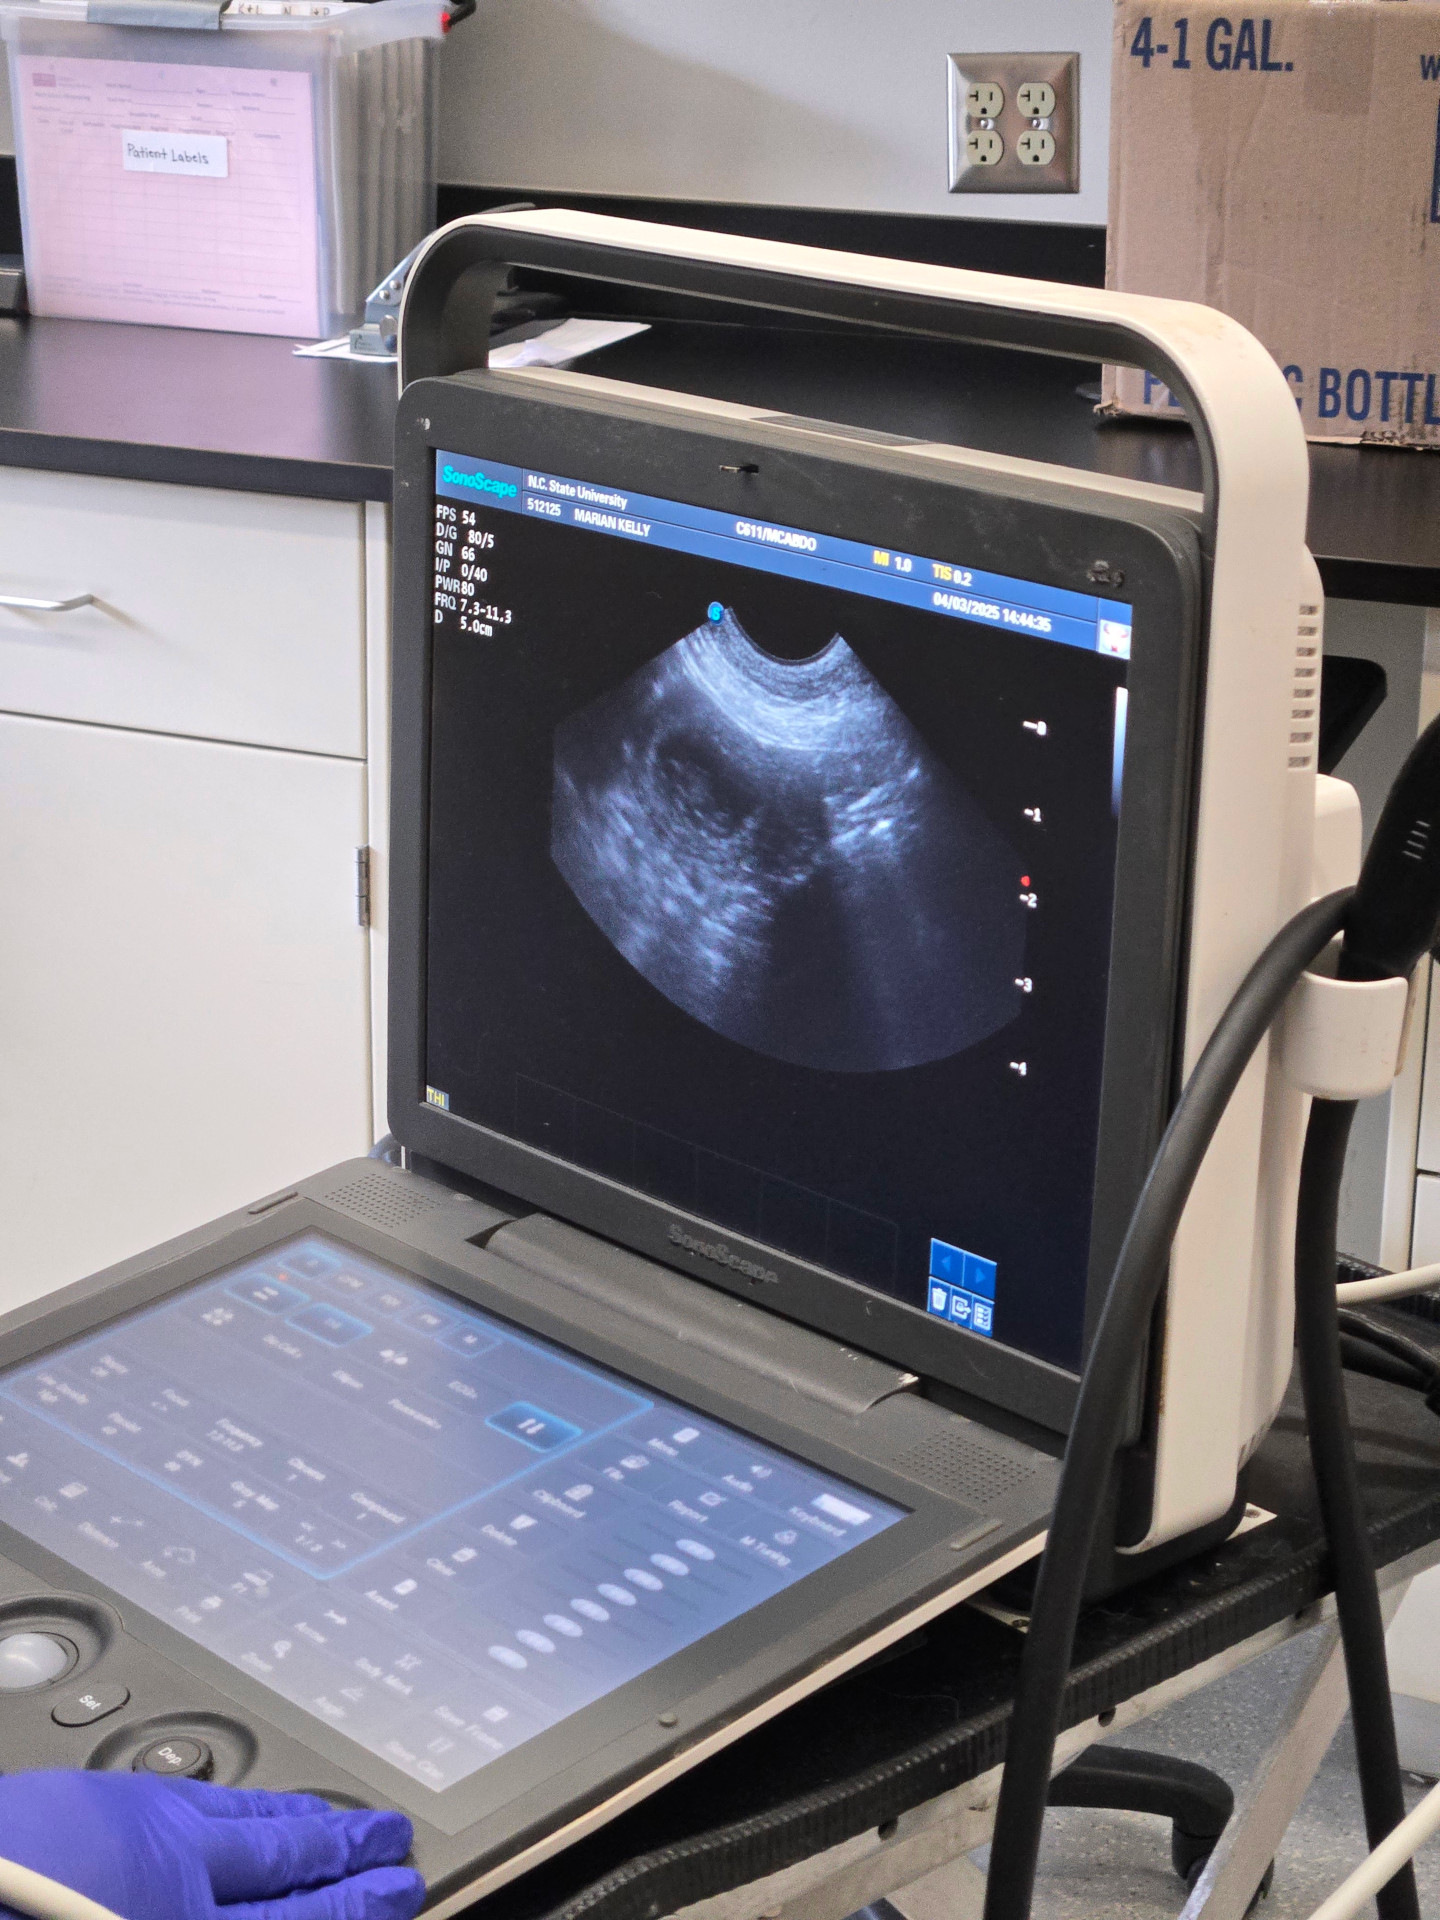

3 Apr

Ultrasound today at NC State University confirmed that Marian is pregnant. You can definitely see two puppies on the ultrasound screen (the round blobs), but the attending (senior) vet said that there may be four puppies. We will do an x-ray when Marian is closer to her due date to get a better count of the number of puppies, and to decide whether to let Marian try to whelp the puppies naturally (free whelp) or whether Marian should have a cesarean section (c-section).

Marian's due date is estimated to be around 8 May.